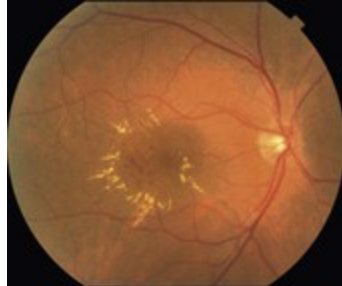

Coat’s disease signs?

Leukocoria

HUGE sign

If onset early enough → may have strabismus

Telangectasia (abnormal dilated capilaries)

"Lightbulb" telangiectasia

Multiple clumped lipid exudates

HTN: In severe cases (Grade 4), you see Macular Star

Fan-like spray of exudates radiating from fovea because fluid is being pushed into Henle's layer of retina